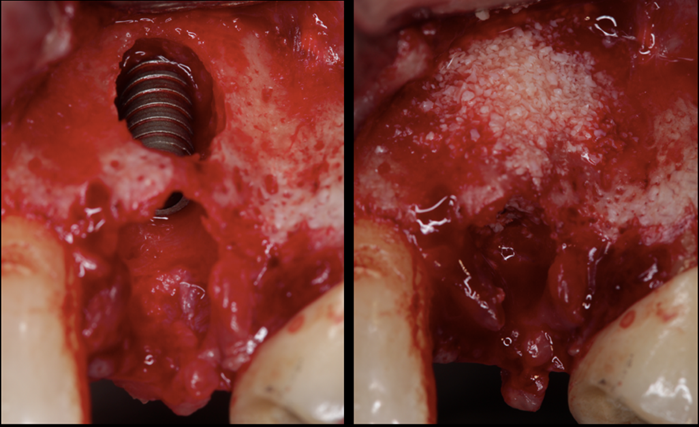

A seguir, as figuras 1 a 5 ilustram o caso:

Por outro lado, sabemos que quando obtemos uma estabilidade primária interessante (acima de 20N) e usamos biomateriais comprovadamente eficazes, os resultados para a implantação imediata associada com ROG são bastante promissores. Além da vantagem de se diminuir o número de cirurgias, temos também, a nosso favor, todo o processo de reparação óssea que ocorre naturalmente, quando extraímos um dente. Assim, apesar de exigirmos muito do organismo no aspecto regenerativo, teremos todo um processo reparador auxiliado pela exodontia, implante de titânio e o biomaterial.